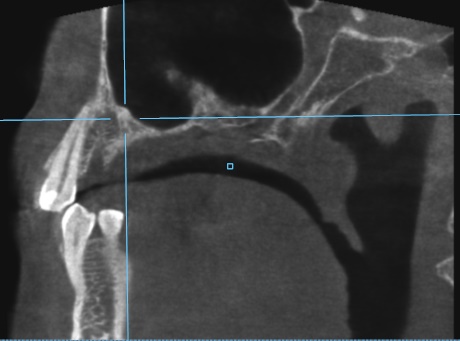

Пропила 2 курса антибиотиков. Хирург сказал, что все зубы в порядке, и отправил домой нервы лечить. Рентгенолог увидела повреждения и сказала не есть больной стороной и вообще не жевать. Это избавило меня от постоянной боли. Но стоит только дотронуться до семёрки, появляется неприятное очущение, как будто он висит на волоске. И в месте удалённой 5 зуд. Как будто кость сломана. Фото с 3д рентгена во время курса антибиотиков.

По этому снимку можно сказать, что немного повреждена передняя стенка, но это не является проблемой. К хирургу обратиться стоит, для того чтобы оценить процесс заживления.